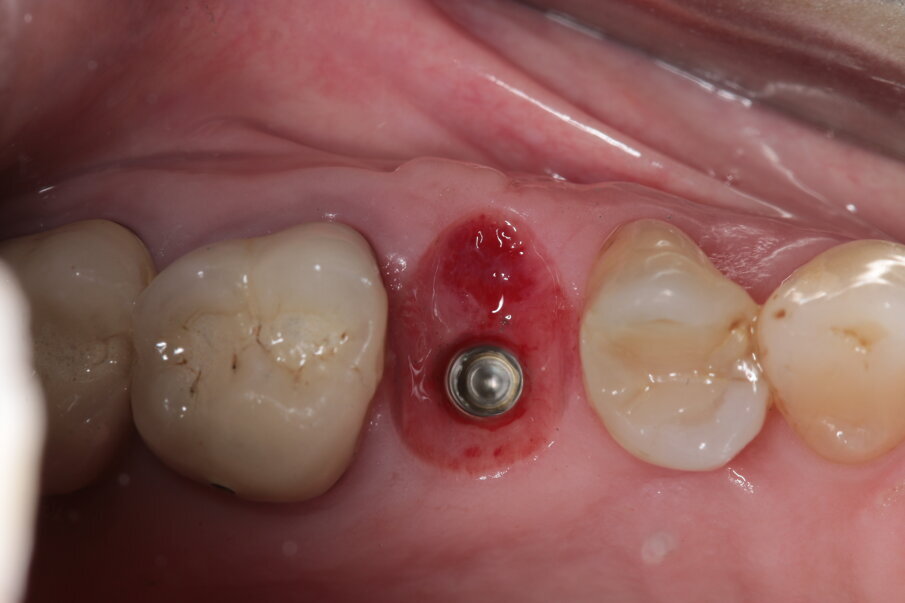

Dalla CBCT preoperatoria, osserviamo che, nonostante un prevedibile ma leggero riassorbimento della corticale esterna, l’ampiezza dell’osso mantenuto è assolutamente sufficiente a posizionare un impianto (Fig. 11). Al momento della chirurgia, è possibile notare come i tessuti siano assolutamente privi di infiammazione e il volume sembra mantenuto, a parte per una leggera concavità sul versante vestibolare, che andremo a compensare con lo spessore dei tessuti molli (Figg. 12, 13).

Viene disegnato un roll flap, posizionato l’impianto tramite una mascherina di guida per la fresa pilota ottenuta tramite stampa 3D, inserita una vite di guarigione transmucosa e suturato il lembo. Dalle immagini intraoperatorie si può notare come la scelta di materiale a rapido riassorbimento abbia permesso l’ottenimento di un osso vitale, sanguinante e con la quasi totale assenza di particelle di biomateriale ancora presenti. L’imprecisione nella sutura della porzione distale del lembo genererà uno spessore maggiorato del connettivo in quella zona, che avrà come effetto un piccolo inestetismo che tuttavia la paziente non nota e che non intende correggere (Figg. 14-17). Al termine dei 4 mesi necessari al completamento del processo di osteointegrazione, viene inserito un provvisorio avvitato con il quale inizia il condizionamento dei tessuti perimplantari.